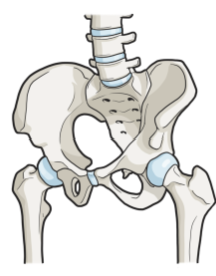

글루코사민 콘드로이친 msm 효능 및 부작용 적정섭취량 등 관련 정보 알아보도록 하겠습니다. 관절은 뼈와 뼈 사이에 위치한 연결점으로, 우리 몸을 움직이기 위한 중요한 부분입니다. 관절은 뼈의 끝에 위치한 연골과 뼈를 연결하는 인대로 이루어져 있으며, 이러한 구조는 원활한 움직임을 가능하게 합니다. 하지만 연령이 들어가거나 부상 등으로 인해 관절의 기능이 손상되면 관절염과 같은 질환으로 발생할 수 있습니다. 이러한 질환은 관절 통증, 감각 이상, 염증 및 손상 등을 일으키며, 일상생활에서의 움직임과 활동에 지장을 주어 생활의 질을 저하시킵니다. 이에 따라 적절한 치료와 예방이 필요하며, 영양소와 운동 등을 통한 관리가 중요합니다.